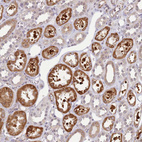

Immunohistochemical staining of human kidney shows strong cytoplasmic positivity in cells in tubules.